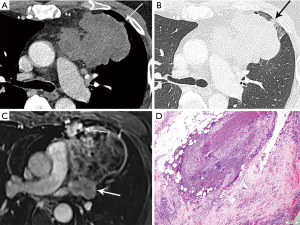

On imaging, these lesions may be large (2–20 cm), heterogeneous and/or infiltrative masses (7) (Figure 6). The majority do not have a capsule on histopathology, and may be either circumscribed or invasive. Calcification is seen in 30% of typical carcinoids (3). Regions of necrosis or hemorrhage can occur in aggressive tumors with high mitotic activity (4,5). Non-necrotic components are expected to enhance avidly on cross-sectional imaging. Half of individuals with typical or atypical carcinoid will have regional nodal or distant metastases, and 10% with atypical carcinoid may show contiguous pleural or pericardial invasion (3). In distinction, three quarters of the more invasive large cell neuroendocrine carcinomas demonstrate local invasion or distant metastases (3). On MRI, these lesions will be T1 iso to hyperintense and T2 hyperintense, and can exhibit heterogeneous signal characteristics (7).

On imaging, thymic carcinoma is more likely to be poorly or irregularly marginated and more likely to have internal heterogeneity due to calcification or cystic/necrotic change (Figure 5A). Thymic carcinomas are often associated with pericardial or pulmonary parenchymal invasion (40%), pleural invasion (30%), and vascular invasion (20%) into the superior vena cava or brachiocephalic veins (3). Additionally, a higher proportion, approximately 19–50%, present with distant metastases, most often to bone, liver, lung, and adrenal gland, at time of diagnosis in comparison to thymoma (3). Pericardial effusion, pleural effusion, or enlarged lymph nodes are also more likely with thymic carcinoma than thymoma.

Thymoma and thymic carcinoma have different MR characteristics. Thymic carcinomas are hyperintense on both T1 and T2 weighted images, distinct from the T1 hypointensity of thymomas, and there may be signal heterogeneity due to calcification, necrosis and/or hemorrhage. Soft tissue components will enhance on post-contrast images, and invasion into adjacent structures may be more clearly delineated. MR can identify distant metastatic disease in the pleura, lymph node stations, and bones included in the area imaged.

The histological diagnosis of thymic carcinoma is characterized by the clearly malignant features of the epithelial cells and the absence of TdT positive lymphocytes (Figure 5B), in contrast to thymoma.